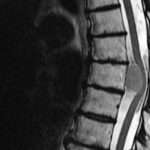

La intoxicación por bloqueadores beta-adrenérgicos es un fenómeno clínico complejo que se asocia a la administración excesiva o inadecuada de fármacos que actúan sobre los receptores beta-adrenérgicos del sistema nervioso…